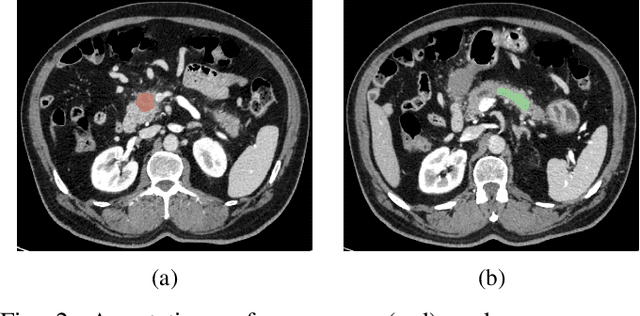

Abstract:Deep Convolutional Neural Networks (CNNs) for image classification successively alternate convolutions and downsampling operations, such as pooling layers or strided convolutions, resulting in lower resolution features the deeper the network gets. These downsampling operations save computational resources and provide some translational invariance as well as a bigger receptive field at the next layers. However, an inherent side-effect of this is that high-level features, produced at the deep end of the network, are always captured in low resolution feature maps. The inverse is also true, as shallow layers always contain small scale features. In biomedical image analysis engineers are often tasked with classifying very small image patches which carry only a limited amount of information. By their nature, these patches may not even contain objects, with the classification depending instead on the detection of subtle underlying patterns with an unknown scale in the image's texture. In these cases every bit of information is valuable; thus, it is important to extract the maximum number of informative features possible. Driven by these considerations, we introduce a new CNN architecture which preserves multi-scale features from deep, intermediate, and shallow layers by utilizing skip connections along with consecutive contractions and expansions of the feature maps. Using a dataset of very low resolution patches from Pancreatic Ductal Adenocarcinoma (PDAC) CT scans we demonstrate that our network can outperform current state of the art models.